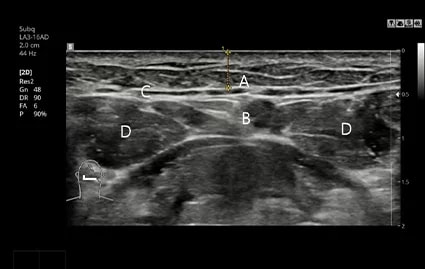

术前进行 CT 与超声波拍摄

通过 CT 与超声波分析筋膜的位置与大小,必要时进行精细的定制化筋膜去除手术。。